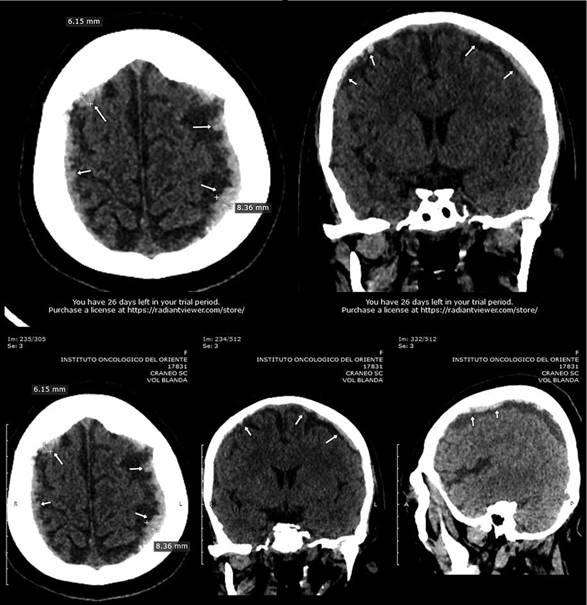

Tras la intercurrencia de dolor de cabeza intenso por más de 24 horas que manifestó la paciente y posterior hemorragia en el ojo derecho, genero una hipótesis a efectos tóxicos tardíos de MTX por lo que se solicitó una TAC de cráneo evidenciando un hematoma subdural agudo frontal bilateral , lo que orienta a una sospecha de MTX retenido tras 10 días posteriores a la finalización de la administración de MTX a dosis de 8 g/m2; este fármaco y sus metabolitos 7-OH- MTX, PG-MTX y Ac-4-N-metil MTX suelen ser retenidos hasta por 47 días post administración y podrían ser los responsables directos de dicho cuadro, por lo que se realizó la determinación de MTX por espectrofotometría UV/Vis empleando el espectrofotómetro T85+ PG Instrument con cubeta de Quarzo de doble haz de Tungsteno y Deuterio, permitió identificar a MTX en plasma humano mostrando una elevada [C] de 9,226 umol/L, motivo por el cual se prosigue rescates adicionales de LVO 50 mg C/6h; transcurrido 6 días más posteriores a las dosis adicionales de LVO; los niveles de MTX muestran una [C] de 7,154 umol/L reducción no significativa por lo que se determinó medir la actividad enzimática por el método CellTitterGlow, mediante fluorometría empleando el fluoroskan Ascent TM FL fluorímetro de placas Thermo Fisher; los resultados muostraron un 55,11% de actividad, siendo este uno más de los motivos por el cual la paciente retiene MTX y es posible responsable del hematoma subdural agudo, convulsiones y neutropenia prolongada, esto corroborado por TAC de cráneo sin contraste, en la que se realizaron múltiples cortes axiales volumétricos del cráneo sin la inyección de material de contraste iodado, y en un segundo tiempo se realizaron reconstrucciones sagitales y coronales. A nivel infratentorial, el cuarto ventrículo y el conjunto de espacios subaracnoideos basales son de morfología y topografía normal. A nivel supratentorial: No hay desplazamiento de la línea media, a nivel extra axial se evidencia colecciones hiperdensas subdural con grosor máximo de 6mm en región frontal derecha y 8 mm en región frontal izquierda, a nivel óseo no se observa lesiones patológicas en la calota craneal, se concluye con la presencia de un hematoma subdural agudo frontal bilateral, correlacionado con antecedentes clínicos, así como también el engrosamiento mucoso en paredes de ambos senos maxilares, celdillas etmoidales derechas en relación a sinusitis y desviación de tabique nasal hacia derecha.

TC de cráneo sin contraste, que evidencia las lesiones hemorrágicas causado por el fármaco acumulado MTX, en el que se realizaron múltiples cortes axiales volumétricos del cráneo sin la inyección de material de contraste iodado, en un segundo tiempo se realizaron reconstrucciones sagitales y coronales. Se evidencia a nivel infratentorial: El cuarto ventrículo y el conjunto de espacios subaracnoideos basales son de morfología y topografía normal. Mientras que a nivel supratentorial: No hay desplazamiento de la línea media, a nivel extra axial se evidencia colecciones hiperdensas subdural con grosor máximo de 6mm en región frontal derecha y 8mm en región frontal izquierda; a nivel óseo no se observa lesiones patológicas en la calota craneal.

Se concluye: Hematoma subdural agudo frontal bilateral, correlacionar con antecedentes clínicos, post quimioterapia, engrosamiento mucoso en paredes de ambos senos maxilares, celdillas etmoidales derechas en relación a sinusitis y desviación de tabique nasal hacia derecha.

TC de cráneo con contraste que evidencia las lesiones hemorrágicas causadas por el fármaco MTX acumulado y desencadenante del hematoma subdural previo, mostrando a nivel infratentorial: El cuarto ventrículo y el conjunto de espacios subaracnoideos basales morfología y topografía normal, después de la administración de contraste no se identifica realces patológicos en el tejido nervioso infratentorial. Mientras que a nivel supratentorial: Persisten algunas colecciones subdurales hemorragias hiperdensas aisladas a nivel frontal bilateral con grosor máximo de 5mm en región frontal derecha y 7mm en región frontal izquierda asociada en este lado a higroma subdural cronico.

Se concluye: Hematoma subdural subagudo frontal bilateral asociado a higroma subdural frontal izquierdo, correlacionado con antecedentes y clínica de la paciente. Entre otros hallazgos: Muestran la persistencia de engrosamiento mucoso en paredes de ambos senos maxilares, celdillas etmoidales derechas en relación a sinusitis y desviación de tabique nasal hacia derecha.